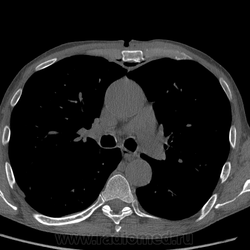

Повреждение грудины, КТ.

После автомобильной травмы с повреждением грудины через пару недель усиливаются боли, температура...